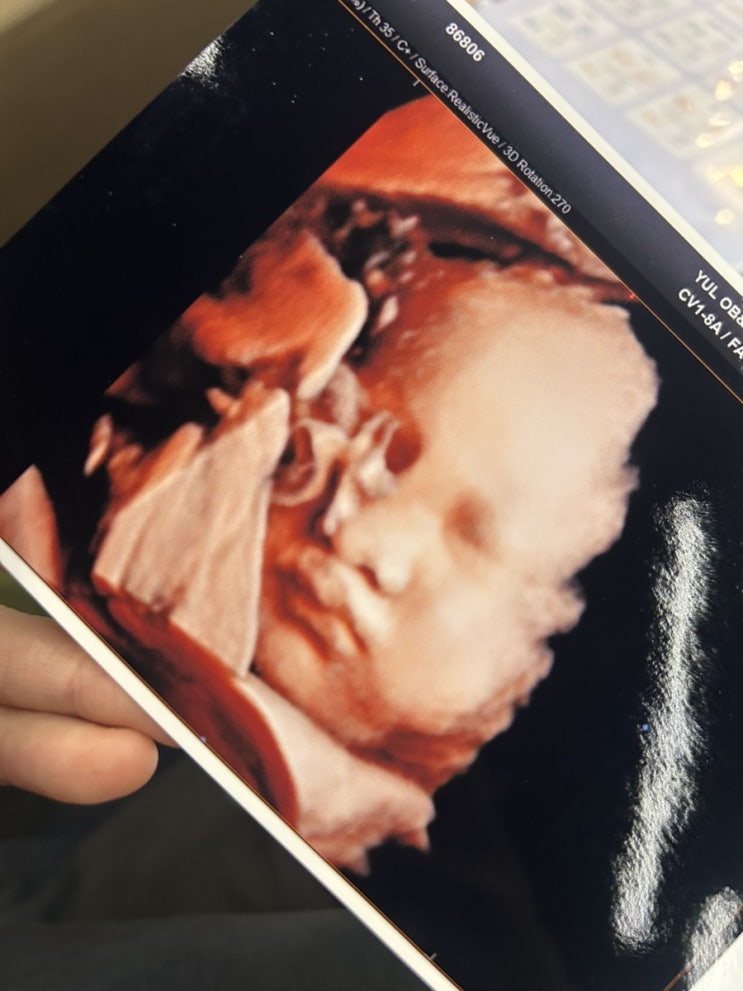

[출산후기] #3 율 산후조리원 6박7일 후기 831호+ 822호(DA룸,S룸/조리원식사, 프로그램, 수유콜)

마지막 출산후기가 될 것 같다. 6박 7일이란 짧은 조리원생활, 4월2일에 출산해서 4월 4일에 조리원으로 이...

[출산후기] #1 원주 율산부인과에서 37주5일 경산모 유도 자연분만 시간별 후기,유도 자연분만 성공 !

병실 생활과 같이 적을까 하다가 자분성공한 것부터 적어두는게 좋을 거 같아서 먼저 남겨두는 똘랑이 자연...